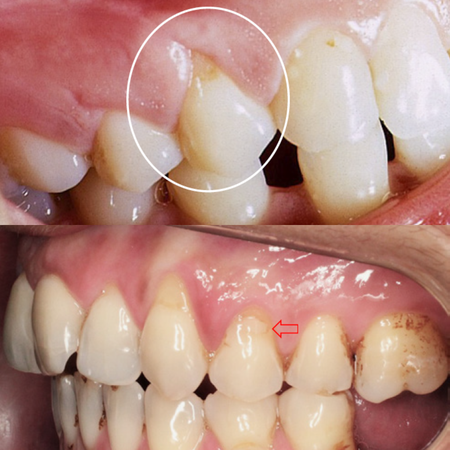

Introduction: There are five 'truly' cervical lesions or diseases, because they originate exclusively in this region. In this second article, we discuss dental abfraction. Methodology: The reasoning regarding its etiopathogenesis in the context of occlusal trauma injury and its early diagnosis by dental hypersensitivity is established. Results and Discussion: The mismatch between the deformation capacity of enamel, dentin and cement under excessive and eccentric occlusal forces represents...

Introdução: São cinco as lesões ou doenças ‘verdadeiramente’ cervicais, por terem origem exclusivamente nessa região. Objetivo: Neste artigo Parte 2, discorre-se sobre a abfração dentária. Metodologia: Estabelece-se o raciocínio quanto à sua etiopatogenia, no contexto da lesão de trauma oclusal; e ao seu diagnóstico precoce, pela hipersensibilidade dentária. Resultado e Discussão: O descompasso entre a capacidade de deformação do esmalte, dentina e cemento sob forças...

Introdução: São cinco as lesões ou doenças ‘verdadeiramente’ cervicais, por terem origem exclusivamente nessa região. Objetivo: Neste artigo Parte 2, discorre-se sobre a abfração dentária. Metodologia: Estabelece-se o raciocínio quanto à sua etiopatogenia, no contexto da lesão de trauma oclusal; e ao seu diagnóstico precoce, pela hipersensibilidade dentária. Resultado e Discussão: O descompasso entre a capacidade de deformação do esmalte, dentina e cemento sob forças oclusais excessivas e excêntricas representa o principal mecanismo para ocorrer a abfração....